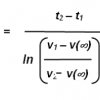

Compound

-----------------

d-methylphenidate

DAT: 139

NET: 408

Uptake DA: 28

Uptake NE: 46

dl-methylphenidate

DAT: 105

NET: 1560

Uptake DA: 24

Uptake NE: 31

Are you supposed to read the uptake-column in the same way? Lower number is high affinity, higher number is lower affinity/level? So... let me see now... This means every enantiomer and racemic mix, increases DA more than it increases NE -levels?

Compound

-----------------

d-methylphenidate

DAT: 139

NET: 408

Uptake DA: 28

Uptake NE: 46

dl-methylphenidate

DAT: 105

NET: 1560

Uptake DA: 24

Uptake NE: 31

Are you supposed to read the uptake-column in the same way? Lower number is high affinity, higher number is lower affinity/level? So... let me see now... This means every enantiomer and racemic mix, increases DA more than it increases NE -levels?

Compound

-----------------

d-methylphenidate

DAT: 139

NET: 408

Uptake DA: 28

Uptake NE: 46

dl-methylphenidate

DAT: 105

NET: 1560

Uptake DA: 24

Uptake NE: 31